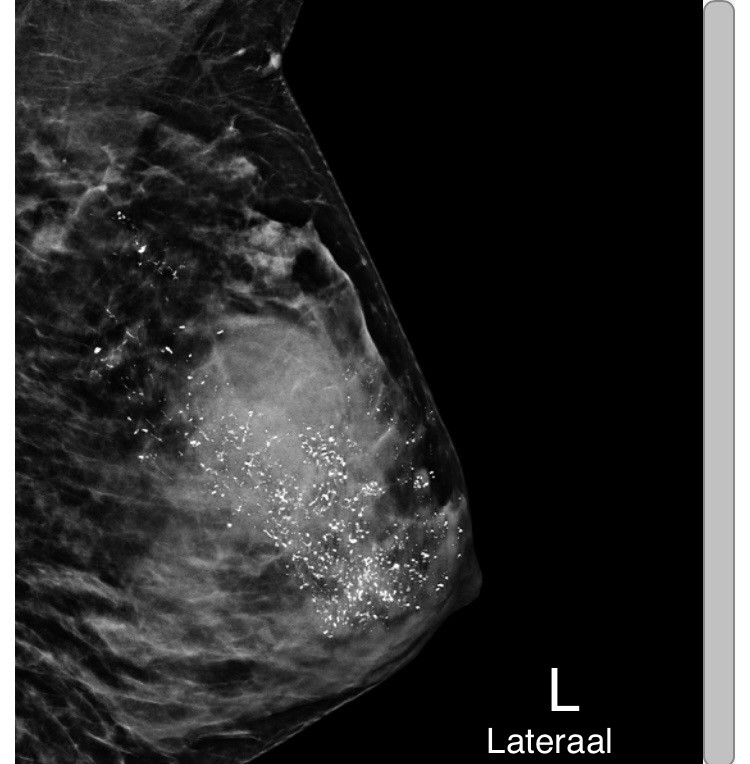

• Borstkanker

• Her2-positieve borstkanker

Ongewenst verjaardagscadeau

Oktober 2025, de maand waarin ik 40 werd, en ook wereldwijd borstkankermaand. Een paar weken geleden had ik nog niet vermoed dat deze 2 gecombineerd zouden worden…